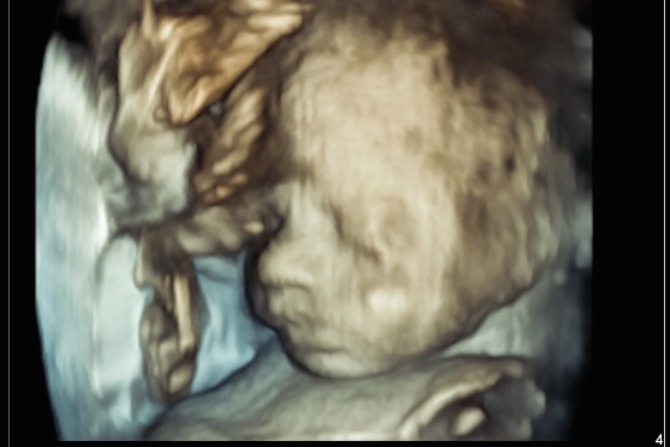

The scan time can vary depending on how baby is positioned in the uterus and the difficulty of the scan. The NCDI can allow one hour appointments so that the sonographer has enough time to perform a thorough examination without any time constrains. The focus is on providing a positive experience, allowing time to see your baby move around on the screen. NCDI do have the capability to perform a 3D image at selected clinics. This is however dependant on the amount of fluid overlying baby’s face, placental location and baby’s position and may not be possible with all patients.

Your baby has grown considerably at this stage, and it becomes more difficult to see its face clearly. The sonographer may be able to point out the profile if there is fluid overlying baby’s face, or it might be easier to point out the lips and nose.